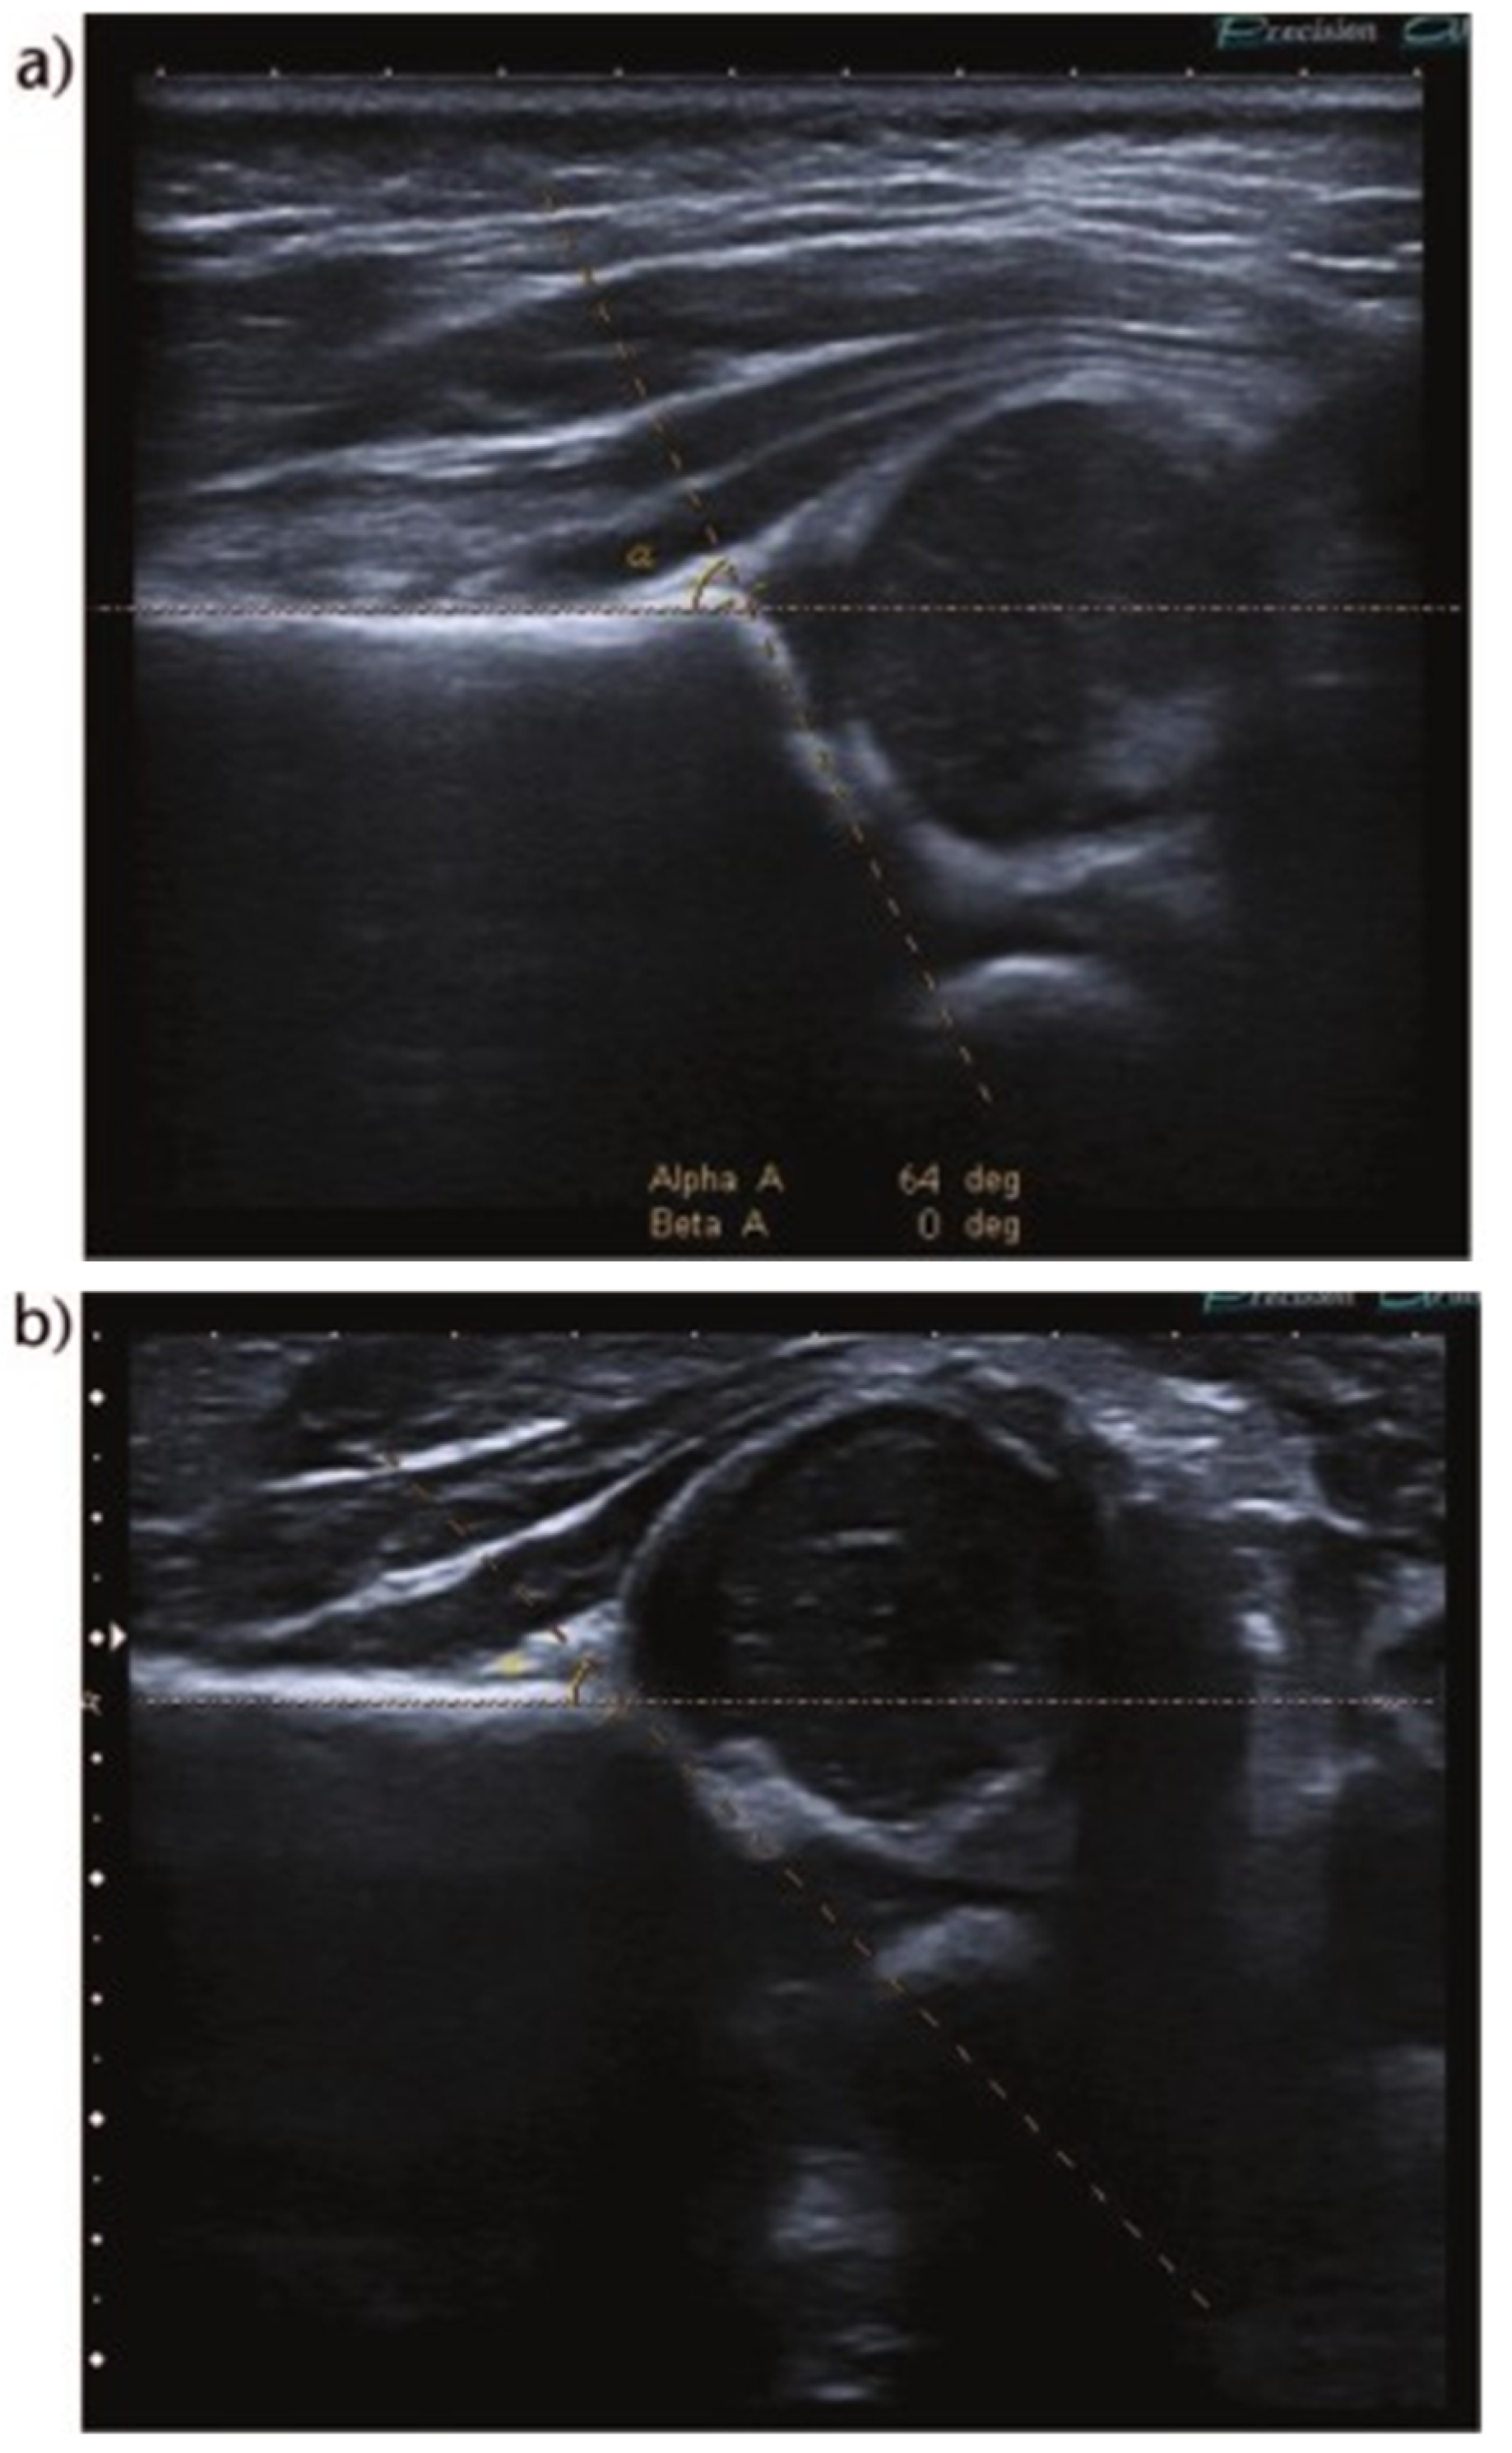

- type I

- alpha angle >60° (normal)

- type Ia: beta angle <55°

- type Ib: beta angle >55°

- type II

- type IIa (physiologically immature): alpha angle 50-59° (<3 months)

- type IIb: alpha angle 50-59° (>3 months)

- type IIc

- alpha angle 43-49°

- beta angle <77°

- type D (“about to decentre”)

- beta angle >77°